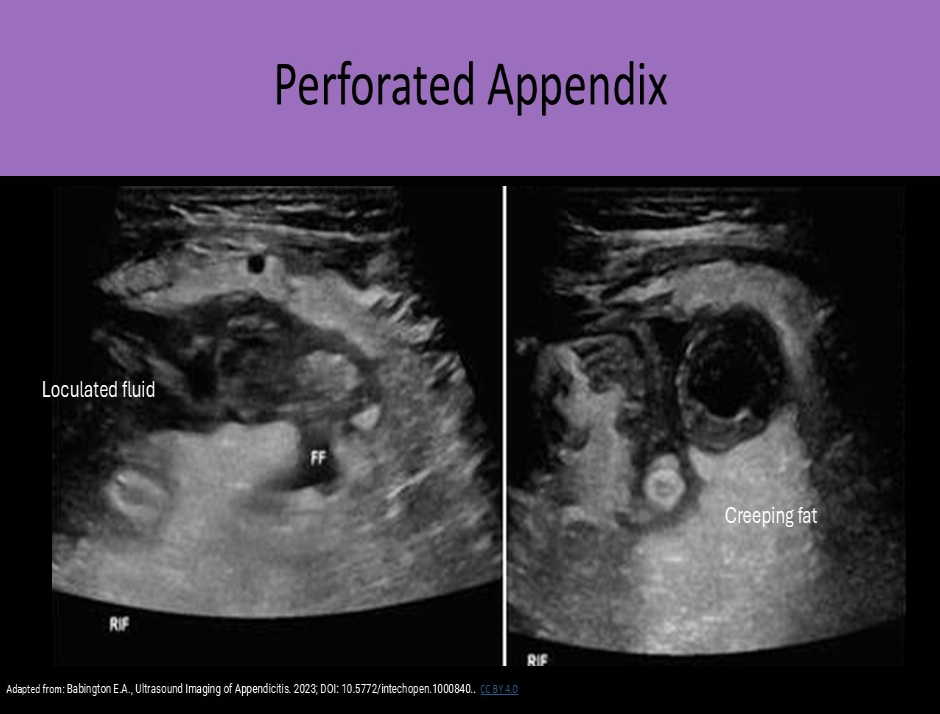

Phlegmon formation, abscess formation, prominent pericecal fat and loculated pericecal fluid collections are sonographic findings that are most suggestive of:

B. appendiceal perforation

Appendiceal perforation is associated with loculated pericecal fluid, phlegmon formation, abscess formation, and prominent inflamed pericecal fat.

Pancreatitis can be associated with similar findings of phlegmon, abscess, loculated fluid, but not normally found in the area of the cecum.